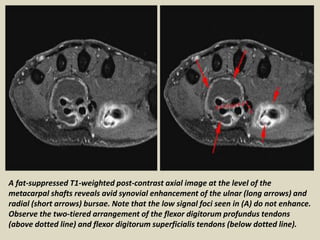

A fat-suppressed T1-weighted post-contrast axial image at the level of the

metacarpal shafts reveals avid synovial enhancement of the ulnar (long arrows) and

radial (short arrows) bursae. Note that the low signal foci seen in (A) do not enhance.

Observe the two-tiered arrangement of the flexor digitorum profundus tendons

(above dotted line) and flexor digitorum superficialis tendons (below dotted line).